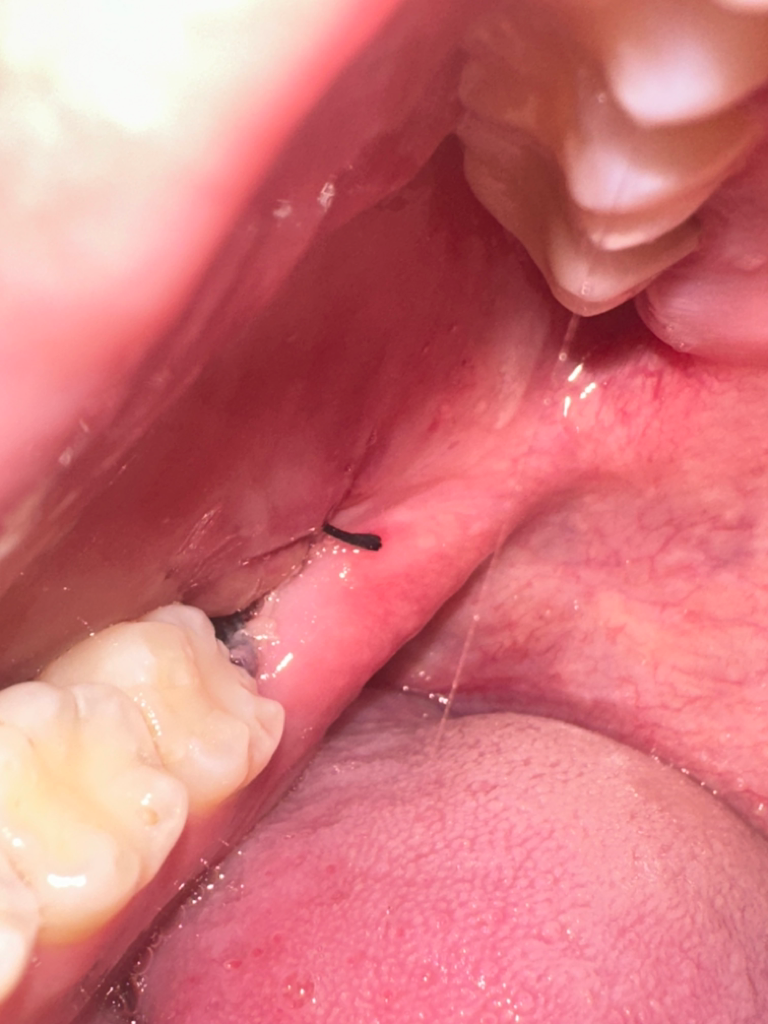

목요일에 사랑니 뺐는데 지금 음식물이 껴있는지 혈병인 헷갈리네요 알려주세용

저기 흰색인가 회색같은거 음식물 인가요 뭔지 잘 모르겠어서 질문 드립니다 그리고 혈병은 제대로 있는건가요?

아니면 혈병이 없는건가요

정상적으로 아물고 있습니다. 희게 보이는 것은 발치한 상처 주위 잇몸색이 변한 것이니 그냥두면 됩니다.

안쪽 약간 검게 보이는 것이 혈병이 굳어져 아물고 있는 것입니다.

혈병은 주로 검붉은 색을띱니다

잇몸은 잘 아물고 있는것으로 보이며 음식물의 여주는 사진으로만은 판단이 되지 않습니다

사진 상으로 봤을 때 혈병 탈락으로 인한 문제가 있어 보이지 않으며

발치 부위에 붓기나 통증이 심하게 발생한 경우 치과 내원하여 검사 받아보는 것이 좋습니다